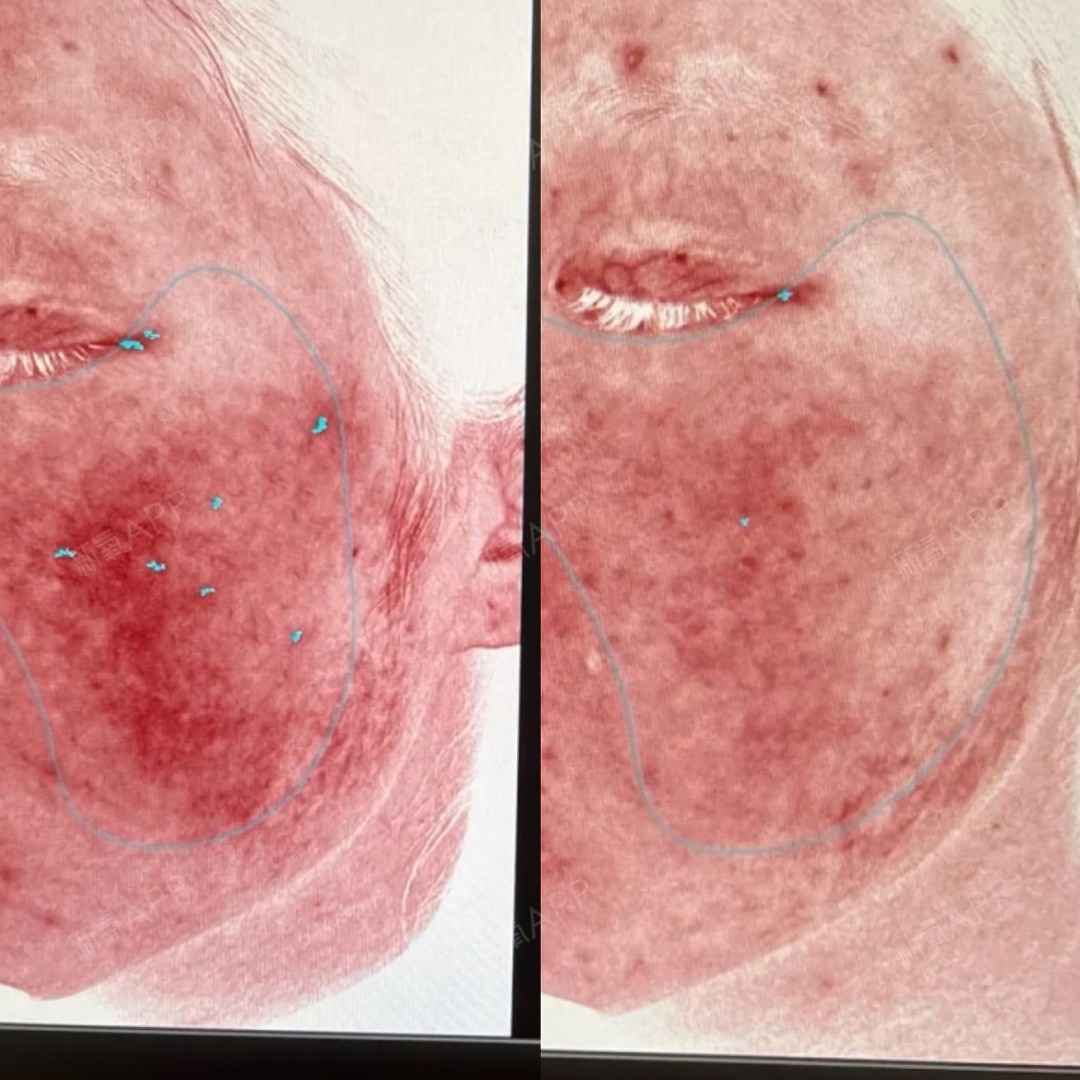

✌️✌️效果反馈:

改善红血丝效果很明显,给大家看下对比,会一直坚持做下去。